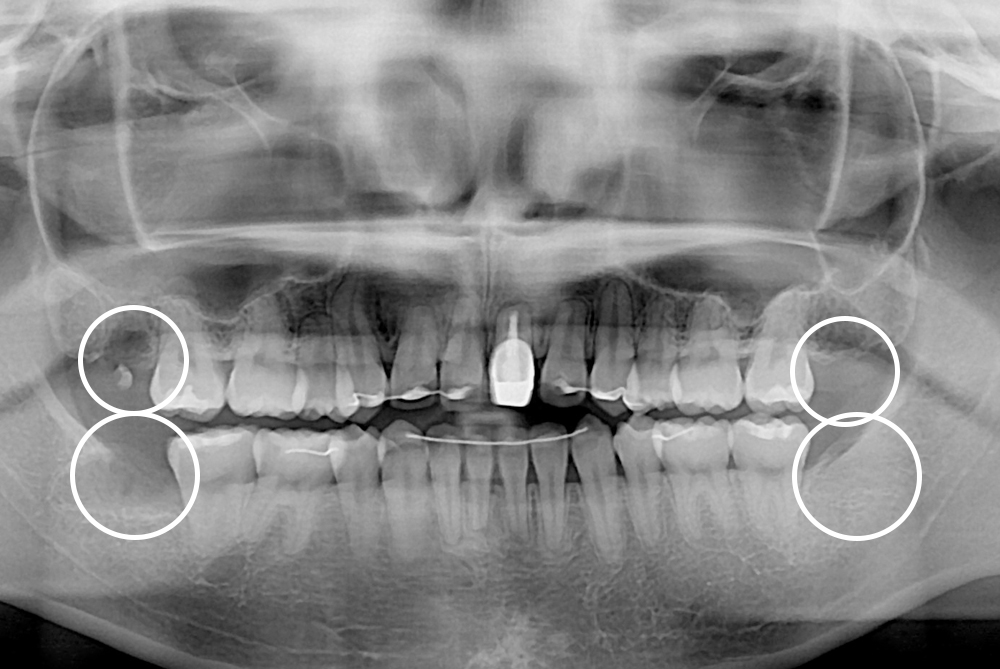

[사랑니] 매복 사랑니 발치

치료전 : 2021-09-18